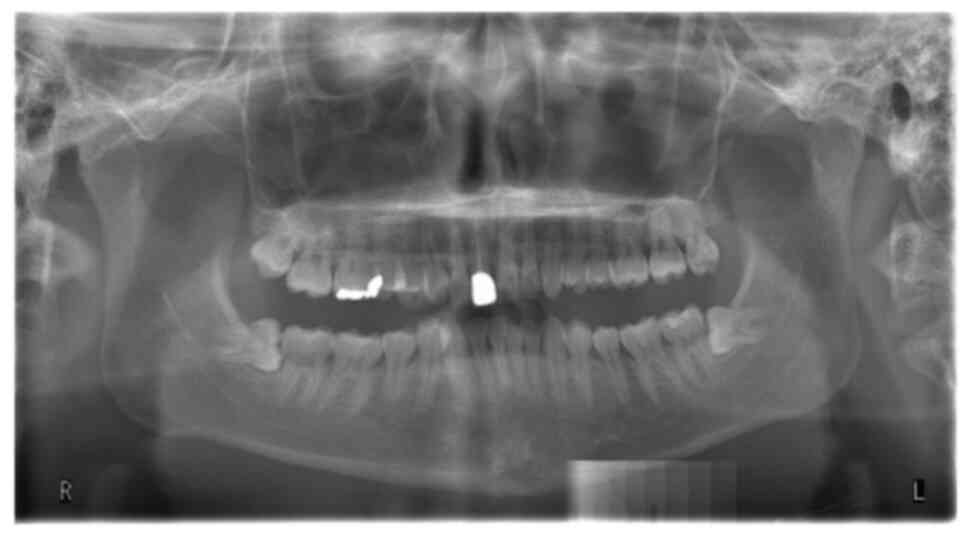

Oral/dental surgical care in patients with chronic medical comorbidities, such as isovaleric acidemia (IVA), can be challenging. In addition to technical complications, different comorbidities also present a complex range of concerning factors/challenges, which can increase the incidence of morbidity and mortality associated with surgery. IVA, a congenital error of metabolism, is a rare organic acidemia with a predisposition towards acute acidosis and life‑threatening metabolic decompensation during stressful conditions, such as prolonged fasting and surgery. In addition, schizophrenia, a major neurological disorder, can result in manifestation of severe dental or periodontal conditions, including pericoronitis. The condition is associated with significant risk factors of postoperative complications, such as dangerous behaviors and adverse interactions between antipsychotic drugs and anesthetic agents. A case of comorbid dental disease with two coexisting chronic and life‑threatening medical conditions, one of which is rare, is an unusual encounter in oral/dental surgery that is seldomly published. Moreover, implementing a safe and effective surgical intervention in such patients requires several informed considerations. However, only a few reported experiences or guidelines exist, reporting appropriate perioperative management strategies to minimize risks. Hence, in this case report, our experience of managing one of these rare encounters of a 20‑year‑old man who suffered from bilaterally partially erupted third molars, associated with chronic pericoronitis and dental caries of both the maxilla wisdom teeth with coexisting IVA and schizophrenia comorbidities is described. Additionally, the presentation and anticipated complications of the comorbid disorders of the patient are briefly reviewed. In this case, the pericoronitis and dental caries were treated by surgically removing the impacted third molars and the antagonist maxilla wisdom teeth under regional anesthesia and application of antibiotics for 3 days. The patient recovered without any postoperative complications after 1 year of follow‑up.

Figure 1

Figure 2

Figure 3

Figure 4